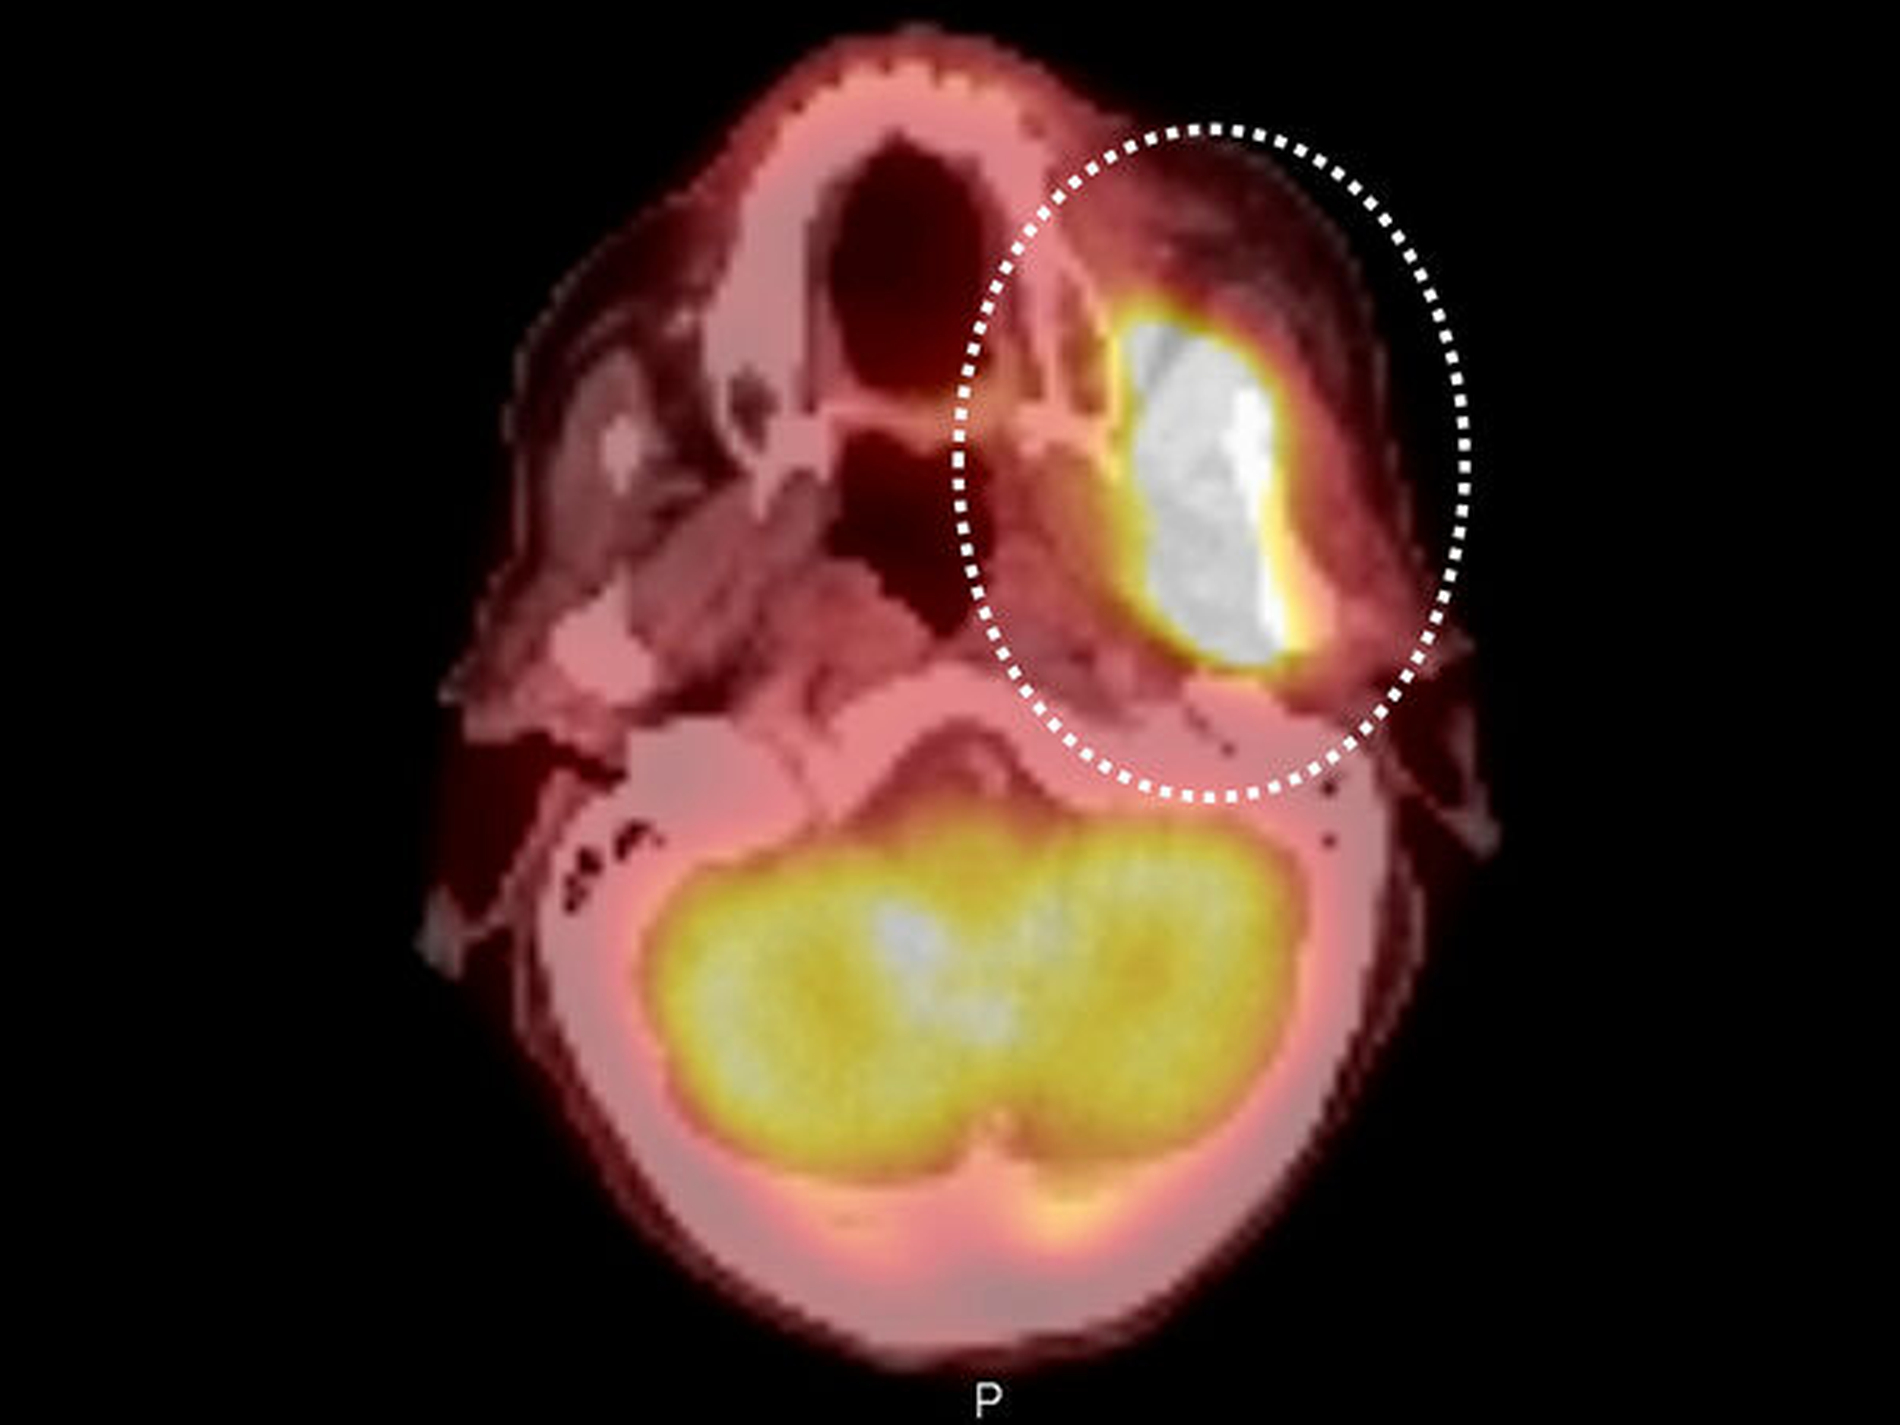

In Vollnarkose erfolgte die operative Entfernung des Zahnes 38 sowie eine umfangreiche Probengewinnung aus den tiefen, umliegenden Weichgeweben und dem Unterkieferknochen. Die im Rahmen des komplettierenden Stagings durchgeführte PET-CT-Untersuchung zeigte zusätzlich die teilweise vorbekannte ausgeprägte osteoblastische Metastasierung des gesamten Achsenskeletts. Dabei ergaben sich keinerlei Hinweise auf eine zervikale Lymphknotenmetastasierung sowie mögliche Fernmetastasen oder bislang nicht diagnostizierte Zweittumoren (Abbildung 4).